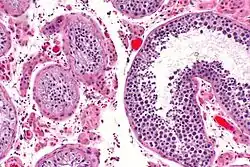

Testicular atrophy

Testicular atrophy is a medical condition in which one or both testicles (or "testes") diminish in size and may be accompanied by reduced testicular function. Testicular atrophy is not related to the temporary shrinkage of the surrounding scrotum, which might occur in response to cold temperature.